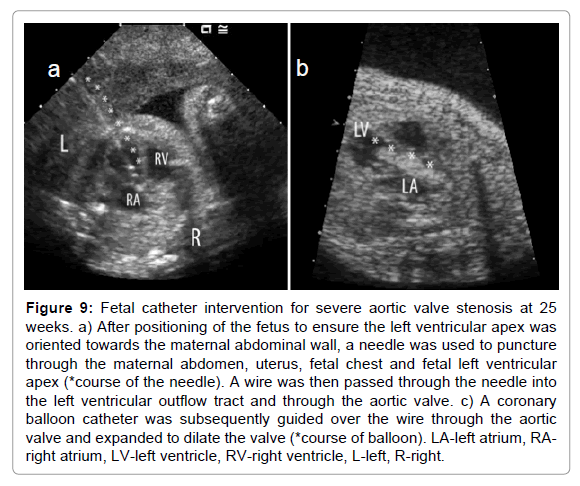

Intervention for fetal aortic stenosis

With the concept that some severe obstructive cardiac lesions such as hypoplastic left heart syndrome can evolve in utero from simple semilunar valve obstruction, attempts at balloon valvuloplasty of the aortic and pulmonary valves were initially reported in the 1980s and early 90s and subsequently reviewed collectively by Kohl et al. in 2000 [120]. The first reported successful series of aortic valvuloplasty to prevent the evolution of hypoplastic left heart syndrome from a single center was described by Tworetzky and colleagues in 2004 [121]. In this report they detailed the technique of intervention in which, after adequate positioning of the fetus, the fetal heart was accessed through the maternal abdomen and uterus and through the fetal chest and ventricular apex (Figure 9). Of 20 affected pregnancies undergoing the procedure, 14 demonstrated technical success and 21% of these fetuses destined otherwise to have hypoplastic left heart syndrome went on to have a biventricular circulation after birth.

clinical-experimental-cardiology-aortic-valve

Figure 9: Fetal catheter intervention for severe aortic valve stenosis at 25 weeks. a) After positioning of the fetus to ensure the left ventricular apex was oriented towards the maternal abdominal wall, a needle was used to puncture through the maternal abdomen, uterus, fetal chest and fetal left ventricular apex (*course of the needle). A wire was then passed through the needle into the left ventricular outflow tract and through the aortic valve. c) A coronary balloon catheter was subsequently guided over the wire through the aortic valve and expanded to dilate the valve (*course of balloon). LA-left atrium, RA-right atrium, LV-left ventricle, RV-right ventricle, L-left, R-right.